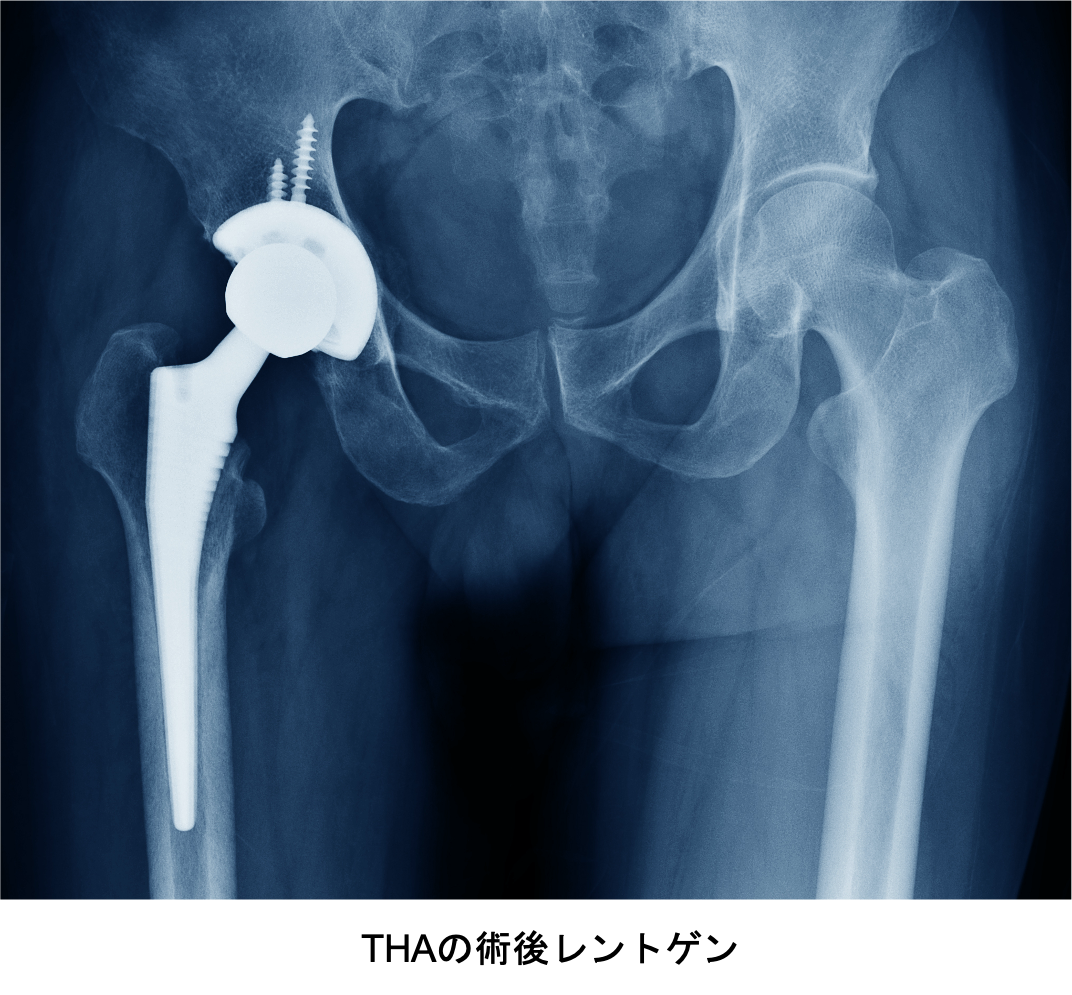

傷んで変形した関節を切除し、人工関節に入れ替えます。 人工関節の材料は金属(ステム、カップ)、セラミック(ヘッド)、超高分子量ポリエチレン(ライナー)が使われており、骨が弱い場合は、骨への固定には骨セメントという樹脂を使用する場合もあります。

術後、大半の方は痛みから解放され、関節の動く範囲も広がり日常生活を送りやすくなり、生活の質(QOL)を改善することができます。 近年は材質の進歩が目覚ましく、人工関節のすり減り(摩耗)やゆるみが生じるリスクは非常に少なく、長期の耐久性が期待できます。20~30年以上の良好な成績も報告されており、最近では50歳代でも人工関節置換術を行うことも珍しいことではなくなっています。年齢に制限はなく、高齢であっても体力さえあれば90代でも手術を受けることは可能です。